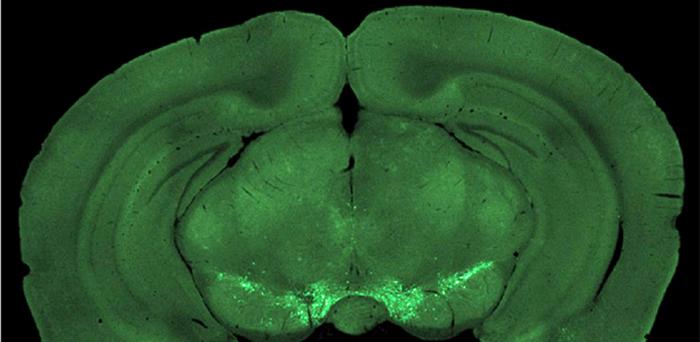

Recent research reported in Neurophotonics dives into this mystery by investigating how mice time their actions in pursuit of rewards, exploring the role of a specific brain pathway called the mesocortical pathway, in the context of self-initiated movement.

They created a task for mice where they could press a lever at will and receive a reward. The mice would receive a better reward if they waited longer before pressing. The research team found that a certain type of brain signal, mediated by dopamine and its “D2” receptors, plays a crucial role in these self-timed actions. That brain signal kicks into gear just before the mice decide to press a lever but, surprisingly, doesn't fire up when the mice respond to cues.

To understand better why that might be, the team used a novel imaging technique to observe the activity of these brain signals — just before the mice initiated their actions. They discovered a gradual increase in activity in certain parts of the brain about half a second before the self-timed presses. Remarkably, this increase in activity occurred regardless of whether the mice pressed the lever quickly for a small reward or waited for a larger one.